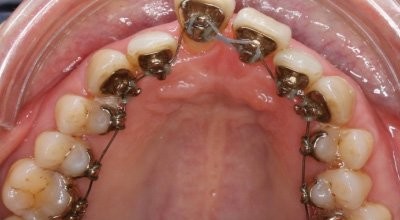

Anhand des vorliegenden Behandlungsfalls soll eine mögliche Therapieform bei einer 60-jährigen Patientin mit vorliegender chronisch genera­lisierter Parodontitis dargestellt werden. Ziel war es, die Vorgabe des Set-ups klinisch umzusetzen und trotz schlechter Knochenverhältnisse auf zusätzliche Verankerungseinheiten wie Minischrauben zu verzichten.

Therapie mithilfe der Incog­nitoTM-Apparatur*, Set-up, Screenshots, seitlich individuelle Bögen, Bogentemplates, Verzicht auf intraorale Ver­ankerungsmaßnahmen (Minischrauben, TPA usw.). Biss­lageeinstellung durch Klasse II-Elastics. Bogensequenz:

Die Behandlungsdauer betrug 15 Monate.